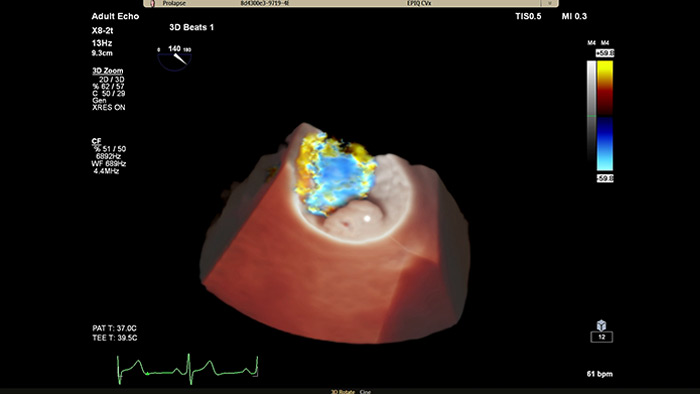

次世代 Live 3D TEE 用の設計 X8-2t Live 3D 経食道トランスジューサの音響設計では、より高い周波数と広い帯域幅により、2D および Live 3D での分解能が上がり、心筋組織の詳細が表現されるようになりました。その結果、Live 3D および Live 3D カラーにおいて、画質を犠牲にすることなく、真の意味でのワンビート画像取得とフィリップス史上最高のボリュームレートが実現しました。ハンドルには、リアルタイムで設定可能なファンクションボタンが搭載され、検査中でも追加機能を使用できます。

インターベンションとのコラボレーション用に開発されたフォトリアリスティックレンダリング 循環器用 TrueVue は、仮想光源を使用してデバイスの視認性を向上させる、新しい 3D 超音波表示方法です。TrueVue は、組織の詳細と奥行き方向の情報を分かりやすく示す画像を提供して、カテーテルおよびデバイスの位置の把握を容易にします。エコー画像がより分かりやすく表示されることで、インターベンション医は確信を持って処置を行うことができます。新型 EPIQ CVx Transcend を見た臨床医の 90%⁵が、新しい TrueVue 3D フォトリアリスティックレンダリングにより組織構造の表示が改善されるため、臨床的確信を強く持つことができると回答しました²。